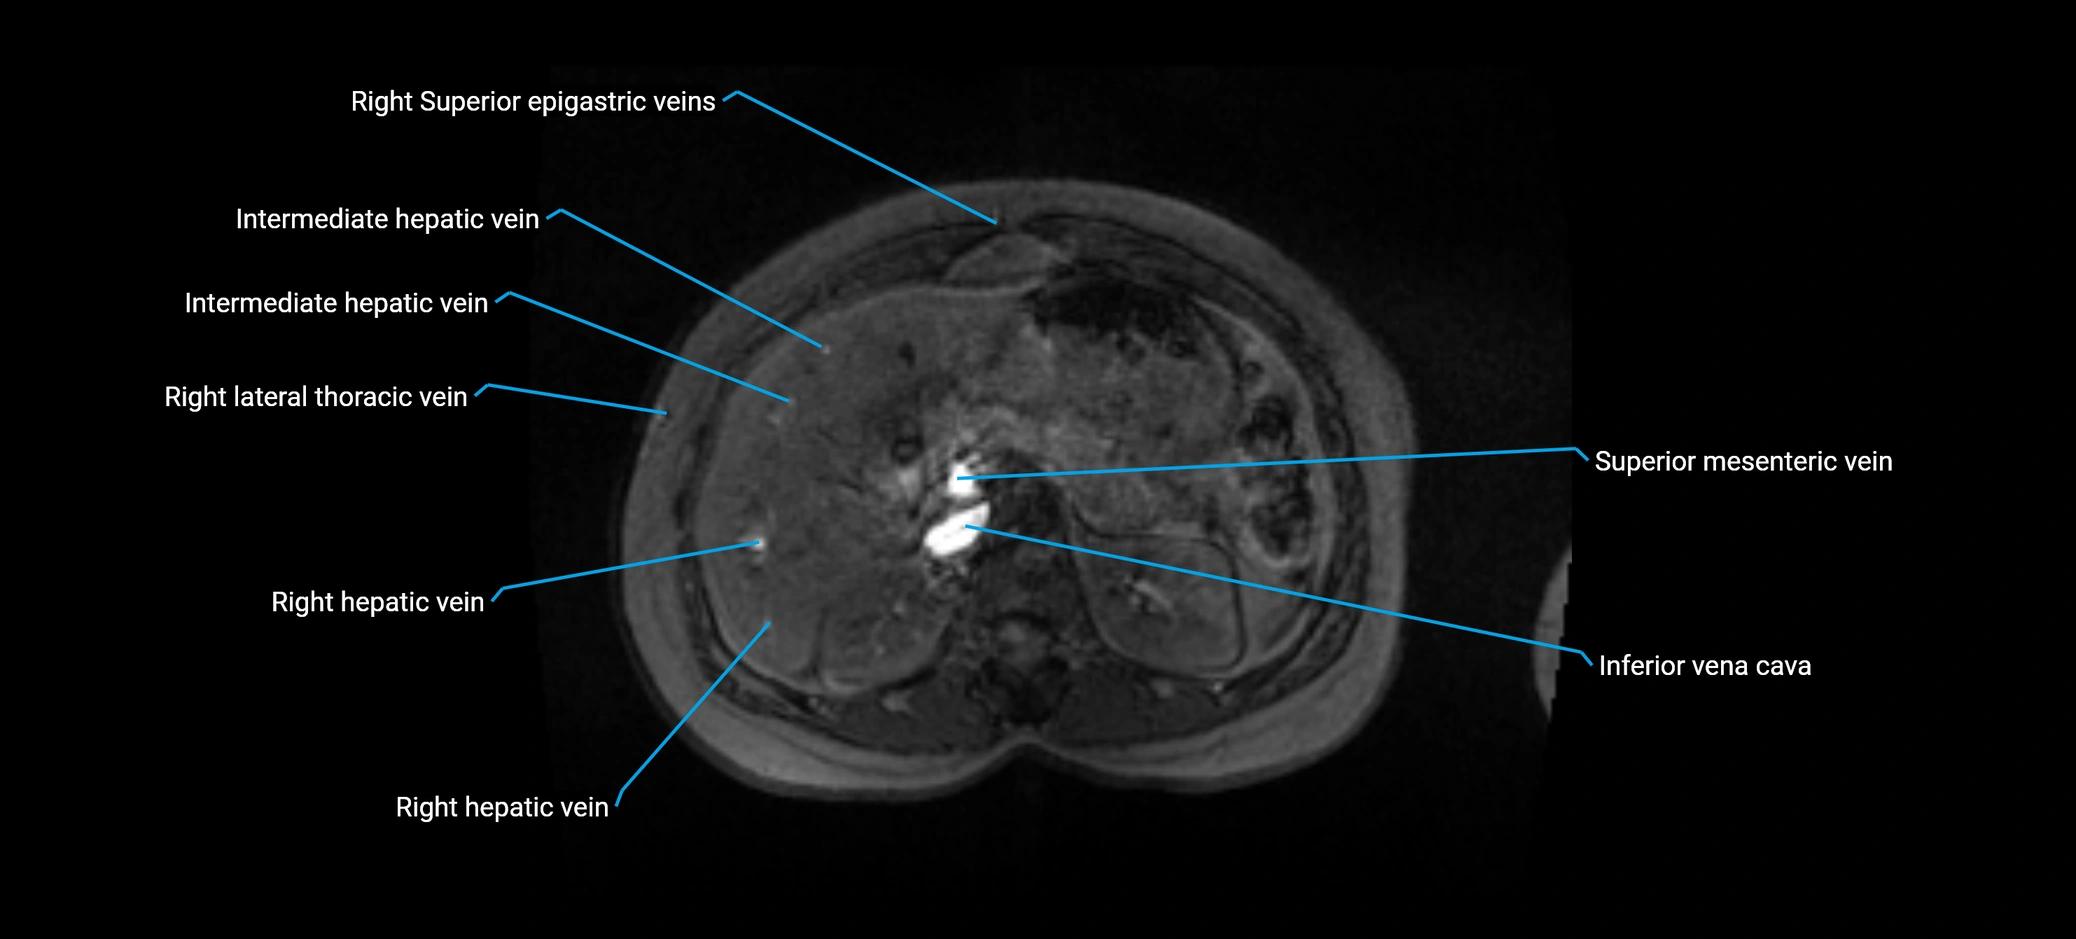

MRI image

image